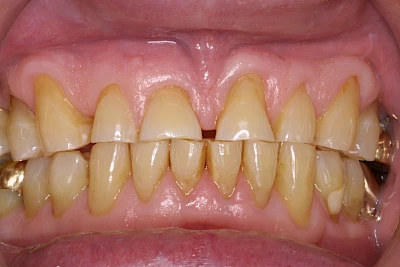

Keilförmiger Defekt

Eine Sonderform sind sogenannte keilförmige Defekte im Bereich der Zahnhälse. Hier geht man davon aus, dass Knirschen und Pressen in Kombination mit falschen Putzgewohnheiten (zu hoher Putzdruck, Verwendung von Zahnpasta mit hohen Abrasionswerten) eine Rolle spielen.